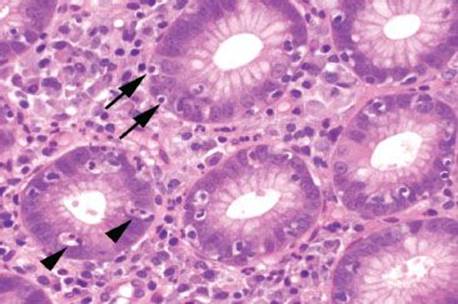

Figure 2.128 Lymphocytic gastritis pattern, Helicobacter. Higher power of previous case. There are intraepithelial lymphocytes present (arrows), and the lamina propria is expanded by a plasma cell predominant mixed chronic inflammatory infiltrate. Careful examination also reveals focal active inflammation (arrowheads). This combination of patterns are most suggestive of Helicobacter infection.